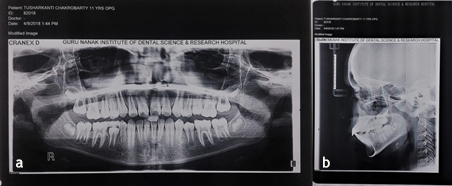

An 11-year-old boy reported to the Department of Pedodontics and Preventive Dentistry, with his parents complaining of their boy being engaged in biting of nails of fingers and toes since 9 years of age. General examination of the boy revealed mutilated finger nails (Figure 2a) and toe nails (Figure 2b). Extraoral examination revealed a dolichocephalic face with short upper lip (Figure 1a). Intraoral examination showed bimaxillary protrusion with Angle’s class I malocclusion bilaterally (Figure 1c). Radiographic examination revealed protruded maxillary and mandibular anteriors (Figure 4a and 4b). Counseling was attempted initially but the patient was not sufficiently motivated. After obtaining informed consent, it was decided to insert an interceptive fixed intraoral deterrent appliance. Efficacy of this treatment was decided to be ascertained by comparison of scores obtained in a questionnaire (Table 1) answered pre- and post-operatively. This questionnaire was based on the Massachusetts General Hospital hair-pulling scale.8 It consisted of seven questions having options with grades from zero to four. The minimum summed up score was zero and the maximum was 28. The patient was asked to fill up the questionnaire. Before fixation of the appliance, the grades summed up to 11.

Figure 4.Preoperative: a) Panoramic view; b) Lateral cephalogram